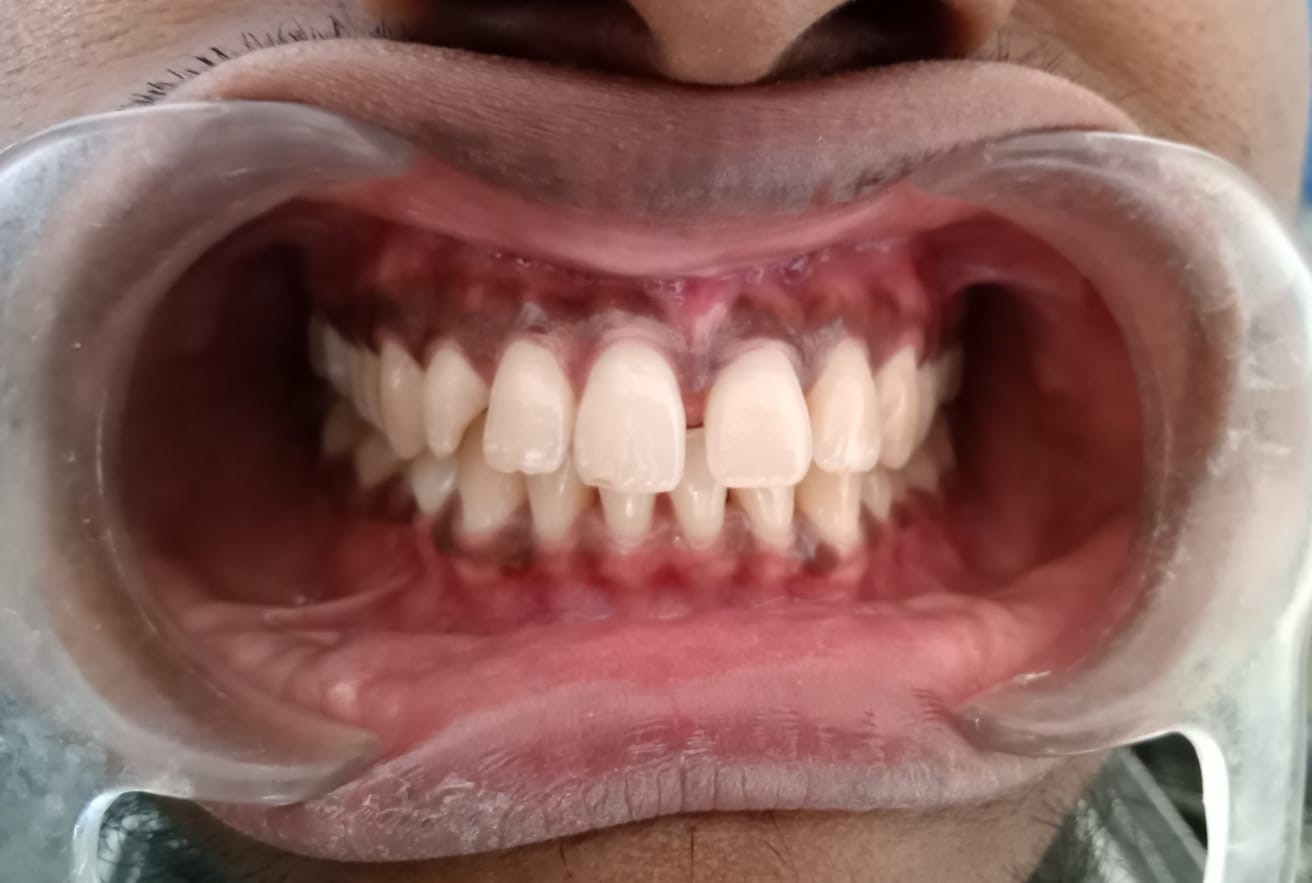

Sairam dental care located in Dharmapuri, with Leading Dentist In Oddapatti, is the Dental Hospital with exclusive root canal, Braces & Invisalign center. Led by renowned Drs Raghuraaman ( Periodontist) and Nivetha Raghuraaman ( Orthodontist) Sairam dental care offers gum treatment with expertise in laser, root canal treatment and digital smile correction with advanced technology aim to focus on aesthetics, comfort and precision. The clinic also specializes in Invisalign treatment, digital smile makeover, laser gum care, dental implants, root canal therapy, extractions and full-mouth rehabilitation blending compassionate care and clinical excellence.

Our professional, experienced, and passionate dentists make us the best choice for Invisalign treatment in Dharmapuri, providing top-notch dental services.